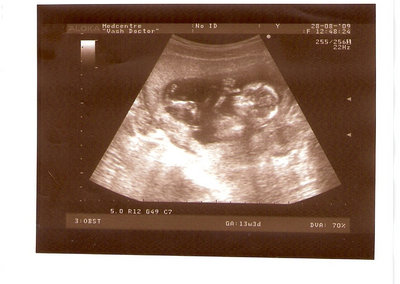

СЫН

| Вложения: |

2.jpg [ 110.14 КБ | Просмотров: 2443 ]

Nikisa писал(а): Foto prosto chudesnoe. A na kakom sroke uznali, chto sin.............. НА 13 НЕДЕЛЯХ.КАК РАЗ ВОТ В ЭТО узи, ОНО УМЕНЯ ВТОРОЕ БЫЛО. ЭТО КОНЕЧНО МАЛЕНЬКИЙ СРОК ДЛЯ ОПРЕДЕЛЕНИЯ ПОЛА. НО Я ПОПРОСИЛА ВРАЧА(ЭТО КТСТАТИВ РОССИИ БЫЛО) ХОТЯ БЫ ПРЕДПОЛОЖИТЬ. ЕЙ ВСЁ ТАКИ УДАЛОСЬ РАССМОТРЕТЬ.НУ ВООБЩЕМ ЧЕРЕЗ НЕСКОЛЬ ДНЕЙ ПОЙДУ К ВРАЧУ, УЖЕ АМЕРЕКАНСКОМУ И УЗНАЮ ТОЧНО. К ТОМУ ВРЕМЕНИ У МЕНЯ БУДЕТ СРОК 18 НЕДЕЛЬ. ХОТЕЛОСЬ БЫ ПОСМОТРЕТЬ НА ДРУГИЕ ФОТО НА ЭТОМ СРОКЕ ИЛИ БОЛЬШЕ. ТАК ЧТО ВЫКЛАДЫВАЙТЕ, ЕСЛИ НЕ ЖАЛКО!